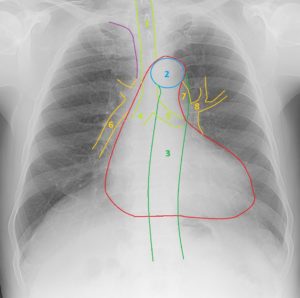

Нормальный диаметр корня аорты: медицинские нормы и отклонения